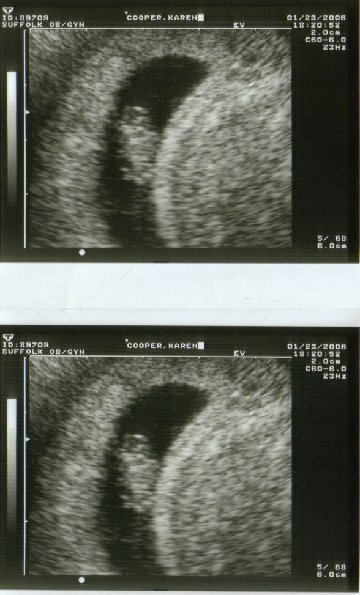

My 7.5 Week Sono

How exciting that was last night !!! Image Attachment(s):

We saw the heartbeat, didn't hear it - but it was pounding. I can't tell which end is which on this - anyone ??

General the bottom is the head, at least thats what my DR told me.

I wanna say the top is the head.....no specific reason other than just the shape

The top is definately the head... You got great pics of your little bean!! Congrats Kat!!!!!

GREAT pics....you can see the baby's little arm and leg buds!! Thats a great pic, congrats!